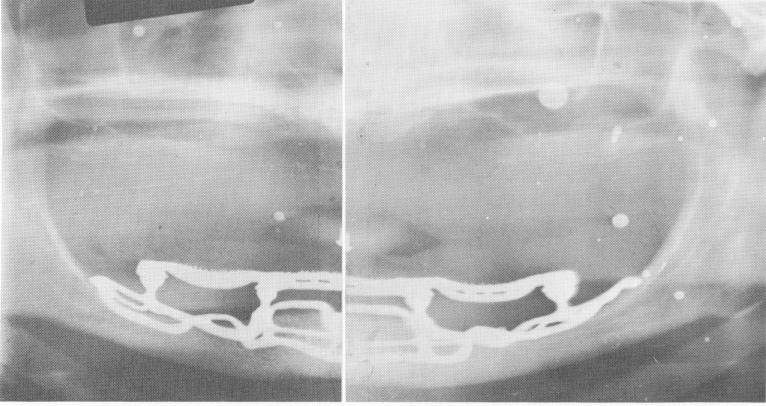

Fig. 12-40. A Panorex showing the close adaptation of the implant denture to the bone of a resorbed mandible.

1 Close adaptation of implant denture to bone of resorbed mandible x ray